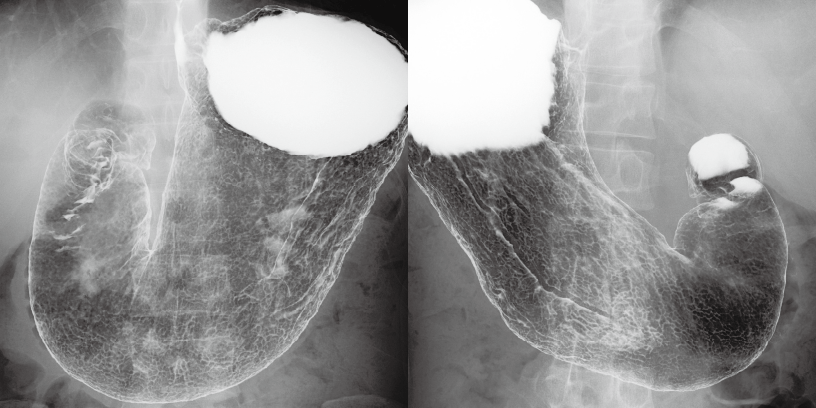

VISTAPANELは、従来からの広いダイナミックレンジを踏襲。データ読み出しノイズを徹底的に抑制し、さらに視認性を向上します。消化管検査や血管造影、一般撮影まで。広い診断領域に対応します。

撮影と同時に適切な階調をリアルタイムに適用することで、適切な輝度とコントラストの付いた画像を表示します。